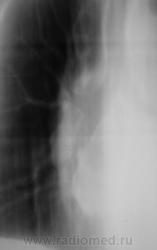

похоже в просет "что-то" растет, наверное показана бронхоскопия? А дополнительная тень не ушко правого предсердия?

Хорошие томограмы, жаль нет бочка посмотреть вентиляцию нижней доли, а так конечно в просвете бронха дополнительная тень, предсердие бы оттеснило весь бронх. Надо рекомендовать бронхоскопию.